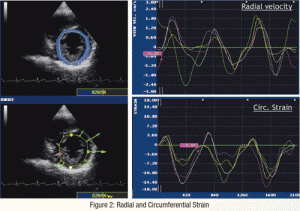

La dernière publication du laboratoire dans le journal « Obesity » s’est intéressée aux déformations et torsions myocardiques chez des adolescents atteints d’obesité sévère en comparaison avec des adolescents sains en utilisant une technique d’échocardiographie de dernière génération.

L’article a été publié sous le titre suivant : « Two-dimensional strain and twist by vector velocity imaging in adolescents with severe obesity ».